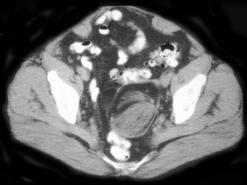

45岁女性患者,自觉腹部胀痛就诊,无发热,血象正常。B超提示左侧附件占位,行CT检查,如图所示,盆腔内见低密度肿块影,其内密度不均,最低CT值约为-150...

问题 45岁女性患者,自觉腹部胀痛就诊,无发热,血象正常。B超提示左侧附件占位,行CT检查,如图所示,盆腔内见低密度肿块影,其内密度不均,最低CT值约为-150.0hu。你认为最佳答案是 ( )

选项 A、卵巢异位妊娠 B、卵巢粘液癌 C、卵巢皮样囊肿 D、卵巢结核 E、卵巢粘液瘤

答案 C